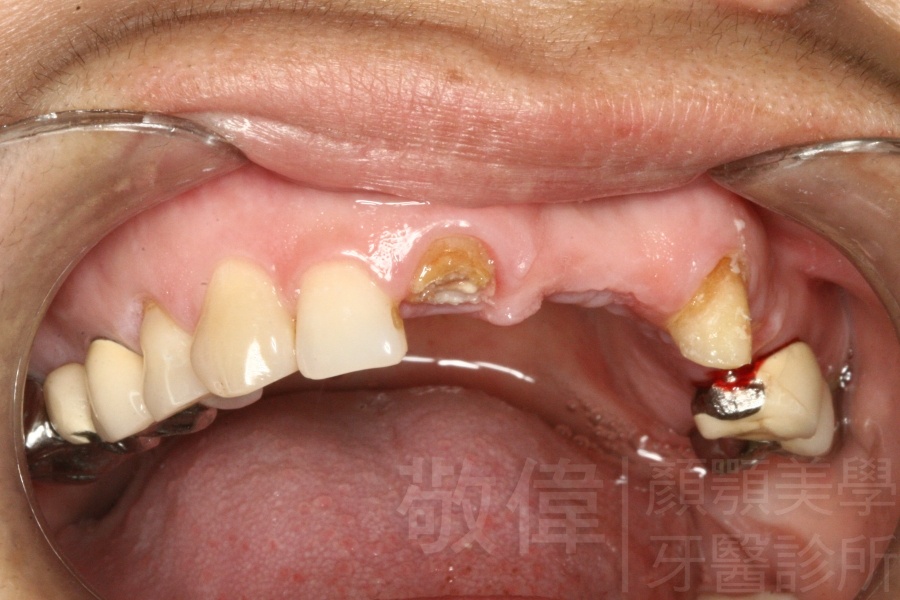

治療前-缺上排前牙   治療後